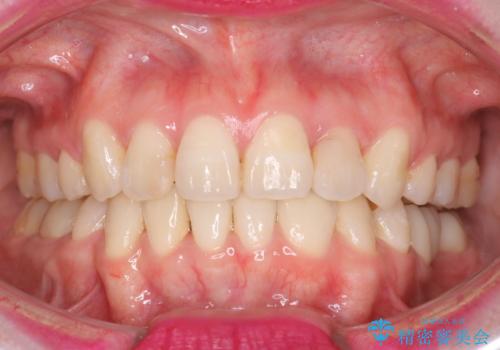

八重歯のワイヤーによる抜歯矯正 矯正治療と並行してセラミック治療も

今回の場合も、ブリッジを除去して矯正後にセラミックブリッジを装着しました。